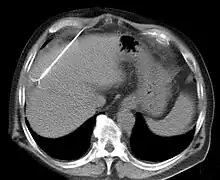

RFA may be performed to treat tumors in the lung,[7][8][9] liver,[10] kidney, and bone, as well as other body organs less commonly. Once the diagnosis of tumor is confirmed, a needle-like RFA probe is placed inside the tumor. The radiofrequency waves passing through the probe increase the temperature within tumor tissue, which results in destruction of the tumor. RFA can be used with small tumors, whether these arose within the organ (primary tumors) or spread to the organ (metastases). The suitability of RFA for a particular tumor depends on multiple factors.